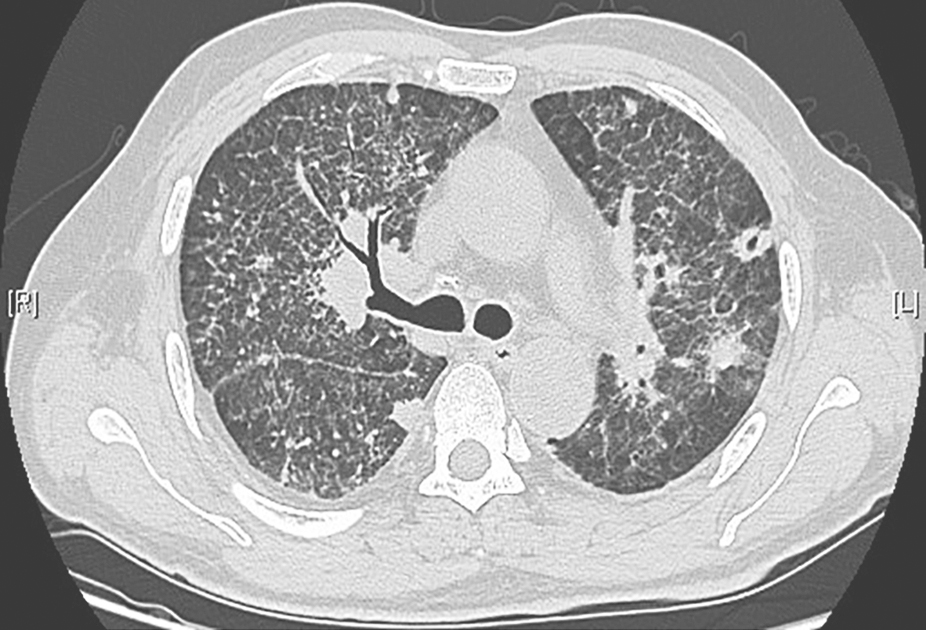

图2结缔组织疾病并发间质性肺炎胸部CT表现

胸部CT可见双肺弥漫性间质性病变,伴肺内斑片高密度影,小叶间隔增厚